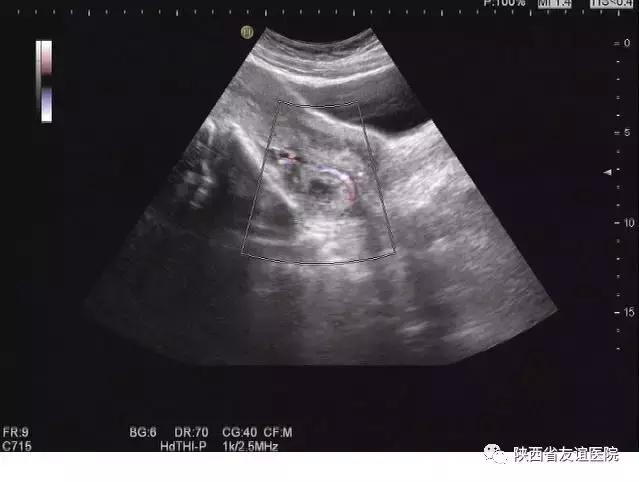

早孕B超图

早中孕B超图

晚孕 B超图

宫外孕B超图